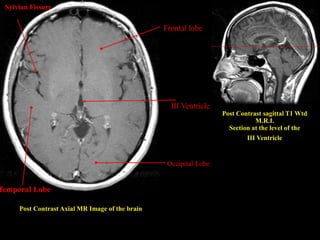

Post Contrast Axial MR Image of the brain

Post Contrast sagittal T1 Wtd

M.R.I.

Section at the level of the

III Ventricle

Occipital Lobe

Frontal lobe

Temporal Lobe

Sylvian Fissure

Fig. 1.6 Post Contrast Axial MR Image of the brain

Post Contrast AxialMR Image of the brain Post Contrast sagittal T1 Wtd M.R.I. Section at the level of the III Ventricle Occipital Lobe III Ventricle Frontal lobe Temporal Lobe Sylvian Fissure

• 41.